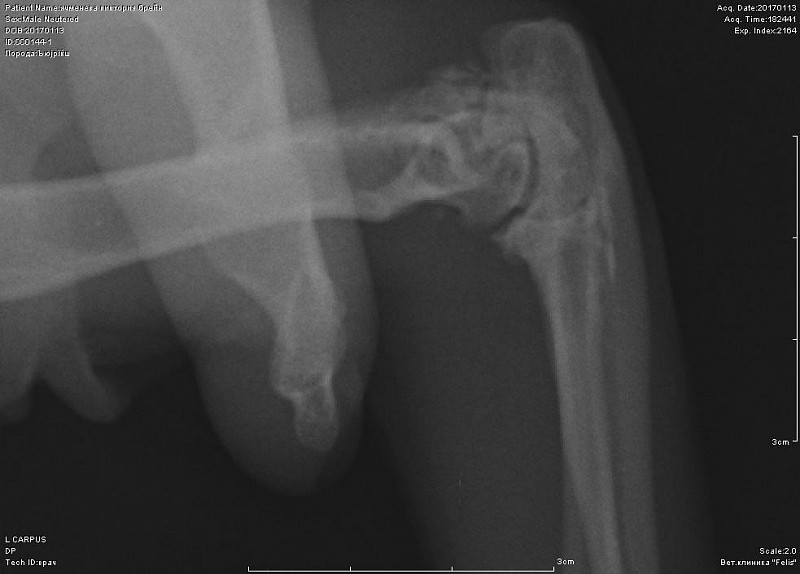

Периодически хромает после долгого лежания.Около 10 дней хромота не прошла, стал не наступать на переднюю лапу-ходит на трех. Повели в к врачу, при осмотре спокоен. Сделали снимок-врач сказал, что был когда-то компрессионный перелом лучевой кости, сказал, что кот хоить нормально больше не будет. Нужно еще мнение, посмотрите снимок, пожалуйста.

Добрый день! не вижу перелома на этом снимке. Нужна еще прямая проекция. Боль именно в запястном суставе?

К сожалению не знаем, где болит-реакции на пальпацию и энергичные движения в суставах не выявили. Именно на этом снимке врач мне указал на компрессию кости-как он сказал кость посередине должна быть квадратная, а она стала треугольной... Я сама нашла атлас посмотрела, что это нормальный вид лучевой кости.

вот в запястном суставе не вижу изменений.А вот локтевом есть признаки артроза. Но все же это не прямая и даже не боковая проекция локтя.